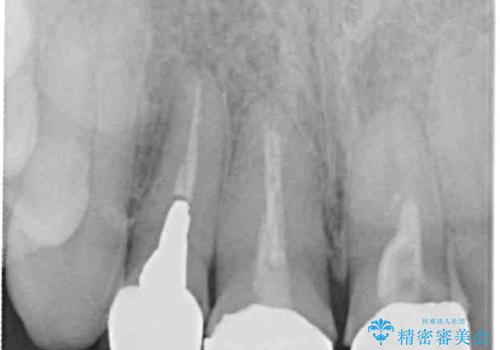

根尖部に病変のある2歯は事前に根管治療を行い、オールセラミッククラウンにて補綴することとしました。

- 根管治療により痛みや腫れがひかない事や、術後に痛みや腫れが生じる事、治療によるファイル破折やパーフォレーションなどの偶発症、術後の歯根破折を生じる可能性もあります